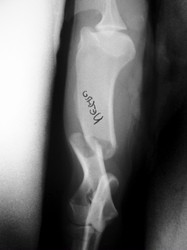

PRÁCTICAS CURSO DE FIJACIÓN EXTERNA PERFECCIONAMIENTO.

Húmero.